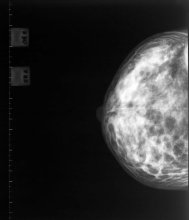

A Missouri University of Science and Technology researcher has developed a new screening method that uses urinalysis to diagnose breast cancer – and determine its severity – before it could be detected with a mammogram.

The debate over breast screening has been re-ignited with the publication of a new study which suggests that screening has not yet reduced the number of deaths from the breast cancer in the UK.